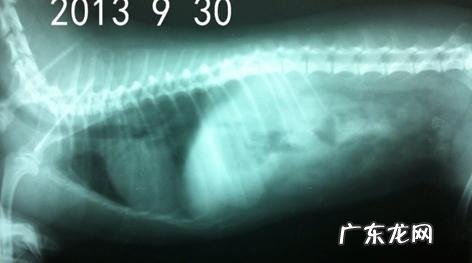

x光图

患犬右侧卧,从X光片沒有见到出现异常